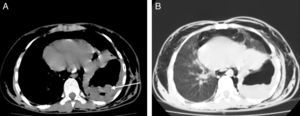

A 15-year-old male came to the emergency department after 3 days with intense chest pain and dyspnea. Thoracic computed tomography (CT) without contrast showed pneumomediastinum, soft tissue emphysema, hydropneumothorax and a giant hydatid cyst with ruptured membranes in the lower lobe of the left lung (Fig. 1A and B; arrow: rupture of membranes). As a result of these findings, the patient was diagnosed with a ruptured hydatid cyst. The treatment consisted of thoracotomy, cystectomy and lavage of the pneumomediastinum. No complications were observed in the patient follow-up.